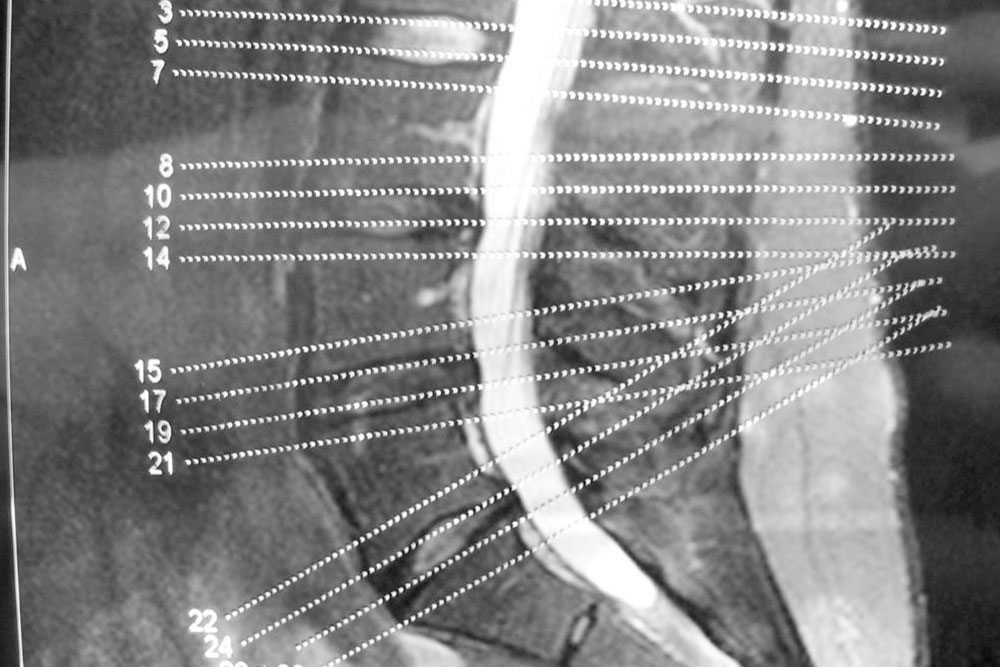

The spinal column consists of spinal discs that perform the task of providing padding between the vertebrae, i.e., the series of small bones that make up our backbone. They also act as shock absorbers and help the back remain flexible. As we age, these discs start gradually losing their elasticity property.

A common cause of this condition is the drying of your spinal discs. As you age, the water in the spinal discs dries out, flattening the spinal disc. A flattened spinal disc cannot absorb shock and they fail to provide padding to the vertebrae. Another cause of this disease can be a crack in the spinal disc. If the walls of the disc tear out, then there is a high chance that the soft core of the disc might push through the cracks and cause the disc to swell or, in the worst case, slip off.